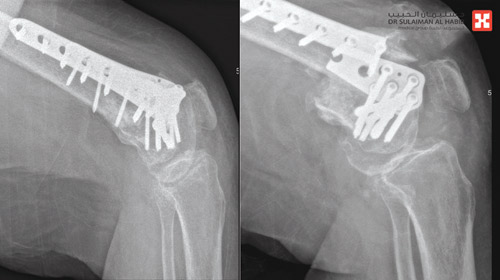

وقال د.علاء إن المريضة راجعت المستشفى وهي على كرسي متحرك بسبب عدم قدرتها على المشي على قدميها، إضافة إلى أنها كانت تعاني منذ العملية الأولى من آلام مستمرة في موضع الكسر، وفور وصولها خضعت للكشف السريري ثم الأشعة السينية والرنين المغناطيسي والأشعة المقطعية، فضلاً عن اختبارات الدم لتحديد ما إذا كان عدم التئام الكسر ناتجاً عن إصابتها بعدوى، وأوضحت نتائج التشخيص مدى عدم الالتئام وانكسار الشريحة المعدنية.

وتابع د.علاء قائلاً إن الفريق الطبي بحث في خيارات علاج الحالة على ضوء نتائج الفحوصات، وإنتهى إلى أن الجراحة هي التدخل العلاجي المناسب، وبالفعل وبعد اتخاذ التدابير اللازمة أجريت للمريضة عملية تم فيها، أولاً إزالة الشريحة المكسورة واستبدالها بأخرى، ومن ثم تثبيت الكسر بشكل قوي وسليم، ومضت العملية التي استمرت لـ» ساعتين» بسلاسة، ووفقاً للخطة العلاجية وانتهت ولله الحمد بالنجاح التام، وتم تحويل المريضة مباشرة إلى جناح التنويم، حيث أمضت منومة لمدة «3 أيام» قبل أن تغادر المستشفى بحالة صحية جيدة ولاحقاً تخلصت من كافة الأعراض التي عانت منها لمدة عام ونصف العام، ثم استعادت قدرتها على المشي على قدميها، وعادت لممارسة حياتها بصورة طبيعية.